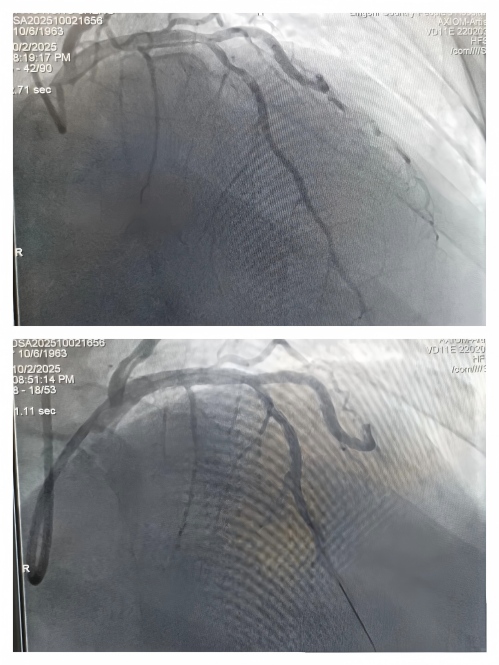

他们穿上重达十几斤的铅衣,关键的诊断性手术——急性冠状动脉造影术随机开始,当清晰的影像在屏幕上亮起,堵塞的血管被成功定位时,心内科介入团队明白,此时必须立即进行PCI手术开通血管。

诊断明确后,真正的攻坚战旋即展开。导丝、球囊、血栓抽吸、支架......一系列操作在团队的默契配合下有条不紊。随着堵塞的血管成功开通,患者濒死般的胸痛症状迅速缓解,生命体征也随之转危为安。

第四位患者行球囊扩张

第五位患者急诊冠脉造影检查